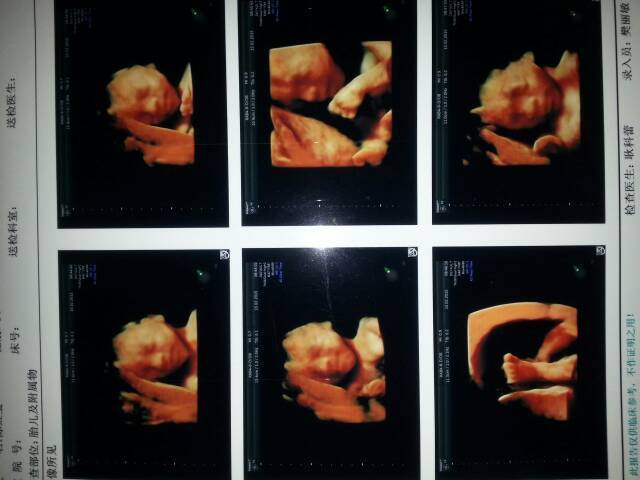

四维照片到了,能猜出男女吗? 四维照片到了,能猜出男女吗? 点击展开 似水流年_dBO7 2015-03-29 09:38 为您推荐: 其他回答 男宝宝,, 宝贝妈AA 2015-03-29 11:28 看不出来。 双胞胎麻麻💋 2015-03-29 10:41 这个是看不出来的 唐爸程妈 2015-03-29 10:25 看不懂。。。。。 少靓舒晴 2015-03-29 10:24 愿宝妈心想事成 凌晨_SGTA 2015-03-29 10:01 加载更多 相关问题 22周四维照片更像谁,猜猜男女宝宝 24周做了四维彩超看男女,医生说没有男孩特征,也没有女孩特征,看不出男女 这是怎么回事?找熟人看的 怀孕几个月做四维彩超能看到宝宝照片最清楚